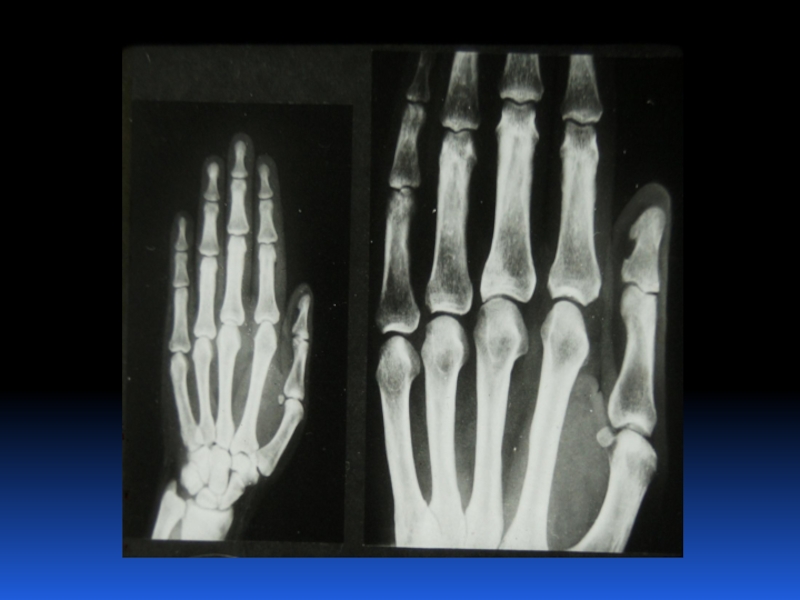

Остеопороз – это системное заболевание скелета, характеризующееся снижением костной массы и нарушением микроархитектоники костной ткани, с последующим увеличением хрупкости костей, со склонностью к патологическим переломам.

Слайд 2 Остеопороз – это системное заболевание скелета, характеризующееся снижением костной

массы и нарушением микроархитектоники костной ткани, с последующим увеличением хрупкости

костей, со склонностью к патологическим переломам.